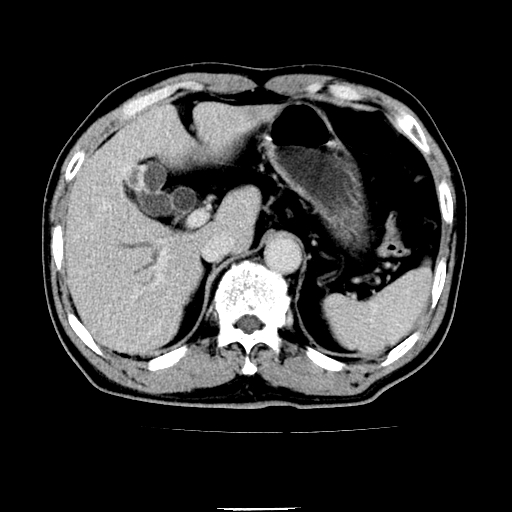

以下是引用chenqiong在2010-3-25 20:56:00的发言:[br]1、胆囊炎,胆囊息肉[br]2、肝内胆管及胆总管扩张,胆总管下端结石[br]3、十二指肠乳头旁憩室

以下是引用zxl51642在2010-3-26 10:47:00的发言:[br]胆囊炎,胆囊息肉,胆总管扩张,但未看到明显肿块,肝内胆管扩张不像恶性,炎性狭窄或阴性结石可能吧,建议mrcp,右肾小囊肿